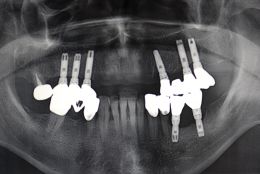

Il paziente si presenta presso la nostra struttura con la mancanza di tutti i denti anteriori dell'arcata superiore da canino a canino.

Il paziente richiedeva una soluzione protesica fissa e desiderava non portare neanche per breve tempo una protesi rimovibile.

Si decide quindi di eseguire una riabilitazione implantare a carico immedito.

Dopo l'inserimento degli impianti viene realizzato un provvisorio immediato fisso cementato su impianti. Dopo tre mesi si esegue un nuovo provvisorio. A distanza di 6 mesi si realizza il manufatto protesico definitivo.